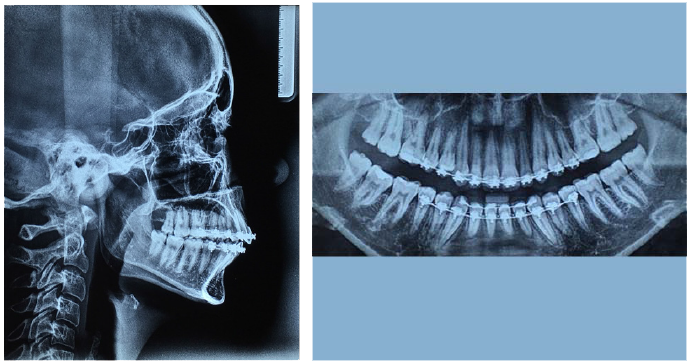

Figure 1B Pre-treatment intra-oral occlusal view photographs.

Upon completion of clinical examination and review of pretreatment panoramic and lateral cephalogram radiographs the patient was treatment planned with a two phase approach which included a maxillary expansion appliance (phase 1) followed by orthodontic treatment (phase 2) and advised of the potentially favorable prognosis of a new non-extraction orthodontic treatment. She decided to pursue attempted maxillary expansion followed by non-surgical, non-extraction orthodontic treatment in order to correct her bilateral molar crossbite, obtain proper overjet and overbite relations, level and align her occlusion and restore satisfactory esthetics by utilizing the bracket technology system of Fastbraces® (Figure 2).